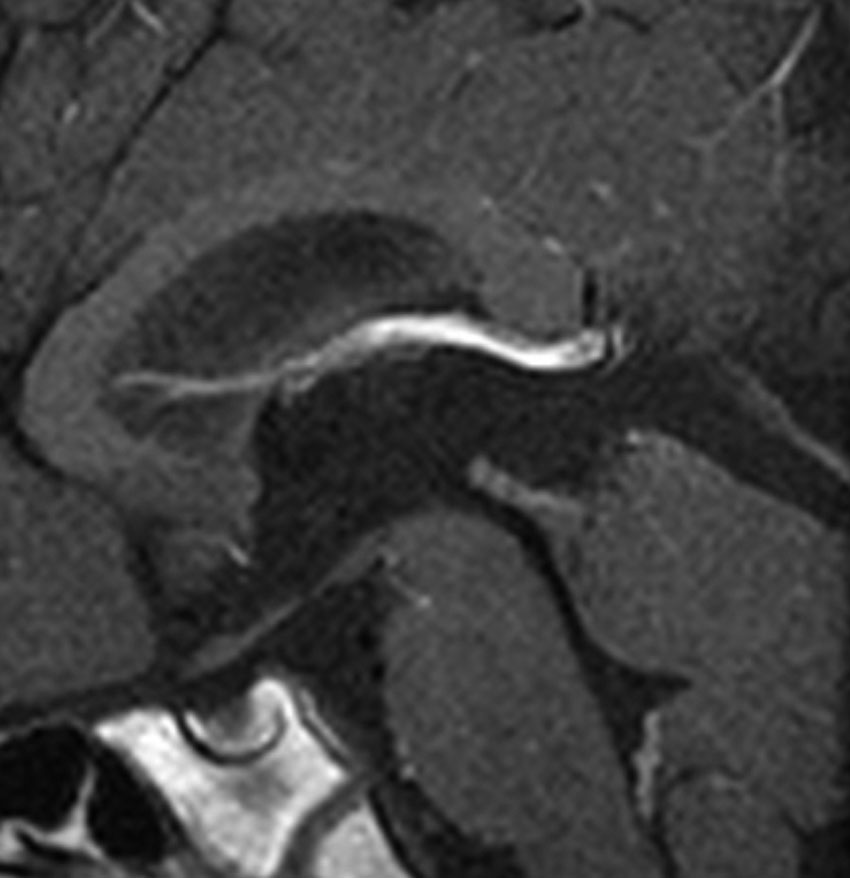

これも偶然発見された無症状の女性の小さい松果体細胞腫ですが,ほとんど実質性でのう胞がありません。右はCISSという画像です。中脳の視蓋は圧迫されて変形していますが,中脳水道がまだ閉塞していないのがよくわかります。